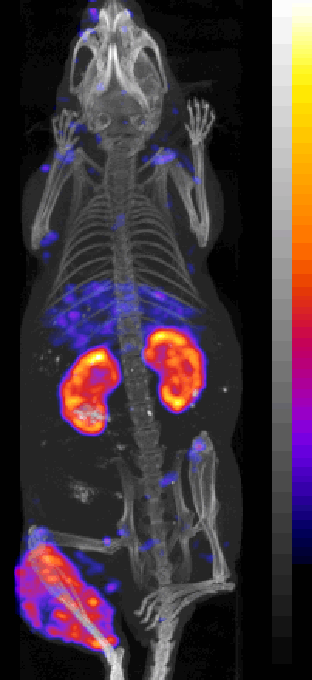

[18F]NaF Bone Scanning